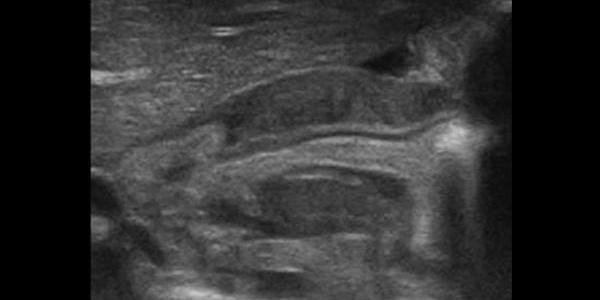

An intussusception is a medical condition in which a part of the intestine goes into another, typically the Ileum into the Ascending colon causing a intestinal obstruction. An easy way to visualize the mechanism is to imagine when you collapse a telescope, that is essentially what happens to the intestines. Imaging Bowel-within-bowel appearance: Alternating layers… Read More Intussusception